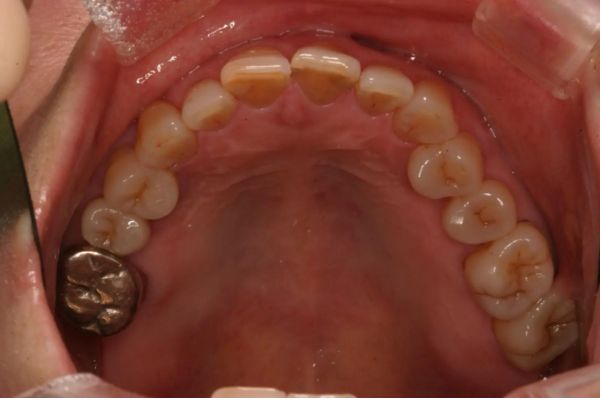

インプラント治療の症例紹介③

Before

After

主訴

むし歯の治療

治療内容

保存不可能な歯の抜歯

下顎にインプラント埋入し咬合再構成

多数歯う蝕および多数歯欠損による咬合崩壊、保存不可能な歯の抜歯により上下無歯顎に。下顎に6本インプラント埋入する事で咬合再構成を行った。